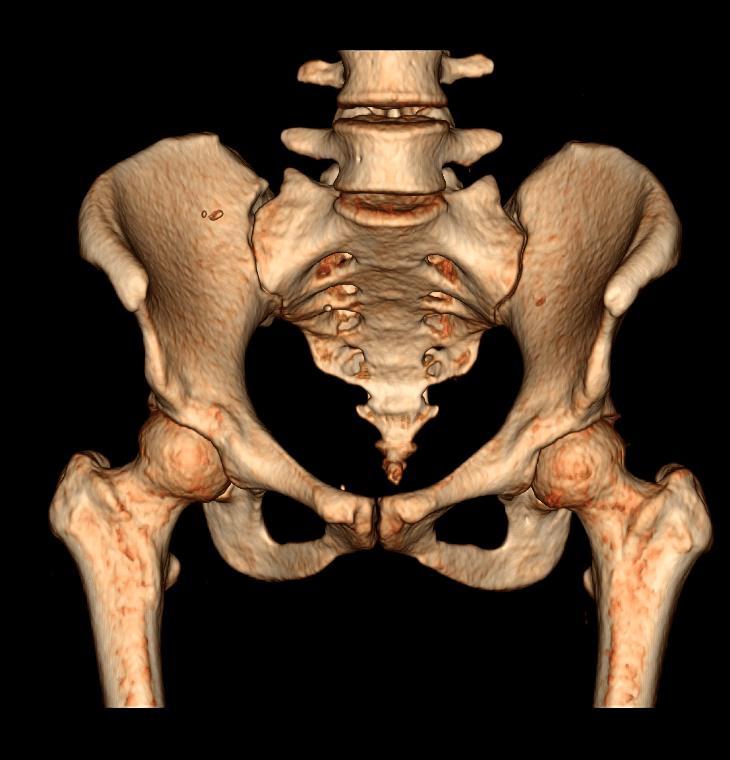

A tomografia da pelve ou pélvica é um exame de diagnóstico por imagem de alta qualidade, que permite analisar o abdômen inferior (fundo da barriga). O exame é indicado para detectar possíveis alterações da bexiga em ambos os sexos. A tomografia da pelve feminina possibilita analisar o útero e ovários (órgãos do aparelho ginecológico da mulher), já a tomografia pélvica masculina permite analisar a próstata e as vesículas seminais (órgãos do aparelho reprodutor dos homens). Contudo, o melhor método para analisar esses órgãos é a ressonância magnética.